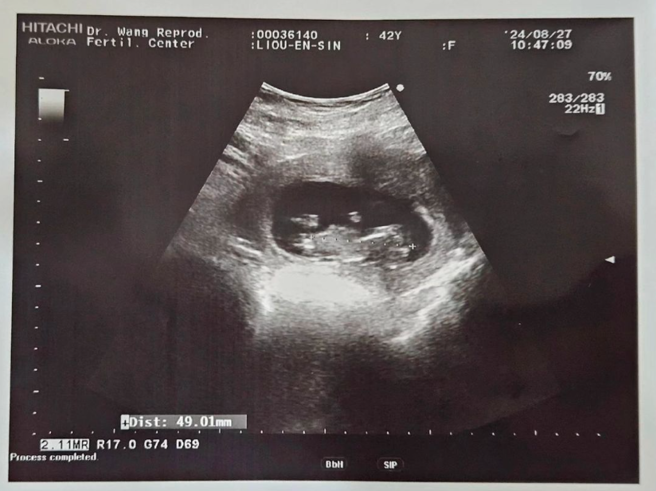

曾获得金钟男配的53岁艺人马力欧(本名:卜国耕),和太太刘恩忻结婚7年,育有一女卜蜜。今(6日)他无预警PO超音波照,证实太太怀第二胎,女儿要当姊姊了。

马力欧今透过社群报喜,贴一张超音波照,兴奋地写道:「二宝贝,欢迎您加入我们卜家!卜蜜要当姐姐了!」并在文末标记不孕症生殖医学暨试管婴儿。喜讯传开后,一排蓝勾勾友人纷纷留言祝贺,像是苏心宁、陈向熙、卞庆华、邱子芯、夏宇童、陈天仁、黄小柔、吴姗儒 Sandy、这群人董仔、欧汉声(欧弟)等人,可见马力欧在圈内的好人缘。

根据《ETtoday新闻云》报导,马力欧太太透过作试管婴儿,植入三次终于成功,目前怀孕十三周,尚不知性别,预产期是明年三月十五日。